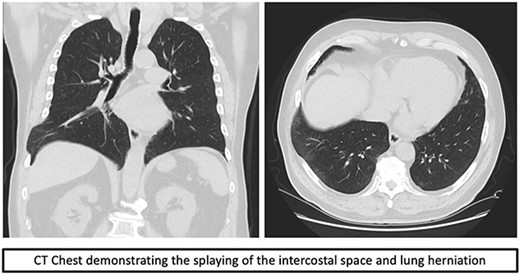

An incision was made directly over the palpable defect in the lower anterolateral chest. The intercostal muscles of the eighth space were found to have been ruptured and splayed throughout the entire length of the space with a clearly identifiable fracture dislocation of the costochondral junction of the eighth rib. Interestingly, there was also a rupture of the anterolateral aspect of the diaphragm with herniation of part of liver into the chest. The parietal pleura was ruptured and it formed part of the hernia sac. There were adhesions of the liver to the lung parenchyma (Fig. 2).

Intraoperative findings of the lung and diaphragmatic herniae as well as the fractured costochondral junction as labeled in image.